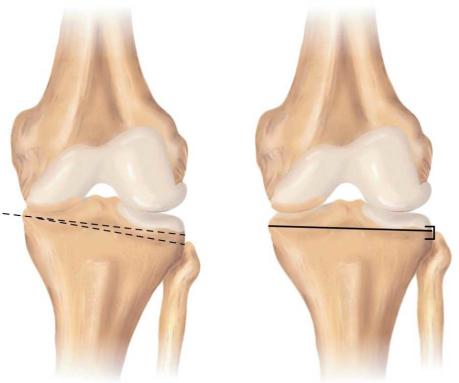

•osteotomija – je postupak koji ima za cilj oblikovanjem koštane strukture postići pravilniju anatomiju zgloba koljena ( slika 23 ).

Ovaj oblik operacije je preporučljiv ukoliko postoji primarno oštećenje jedne regije koljena ili ako se dogodila fraktura koljena koja nije pravilno zarasla. Osteotomija nije konačna operacija i daljnji operativni zahvati će možda poslije biti potrebni.

Slika 23.